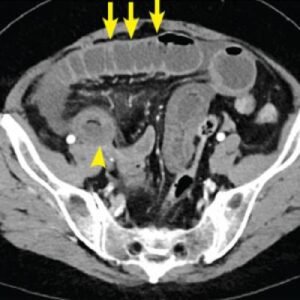

Abdominal pain is a common symptom that can be caused by a variety of underlying conditions affecting the organs within the abdomen. CT (computed tomography)

Virtual colonoscopy, also known as CT colonography or CTC, is a non-invasive imaging technique used to visualize the inside of the colon and rectum for